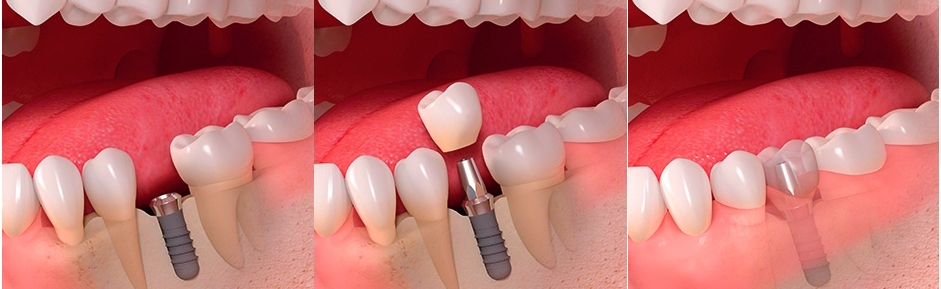

Стоматология «5 Принципов» в Симферополе гордится своими достижениями в области имплантации и постоянного совершенствования качества обслуживания. Наши клиенты получают индивидуально подобранные решения, основанные на передовых технологиях, годах опыта и внимании к деталям. Мы предлагаем комплексный подход: от подробной консультации до восстановления жевательной функции и эстетики улыбки.Каждый этап начинается с точной диагностики: цифровая томография, планирование в 3D, моделирование улыбки. Это позволяет увидеть предполагаемые результаты до начала операции и минимизировать риски.

При имплантации мы используем современные системы имплантатов с высоким процентом приживления и минимальным временем восстановления. Наши специалисты владеют техниками одномоментной фиксации и протезирования без необходимости временной съемной конструкции, что обеспечивает быструю адаптацию и комфорт пациента.В портфолио клиники — примеры успешных восстановлений: имплантация одиночного зуба с естественным оттенком коронки, комплексная реконструкция зубного ряда, а также имплантация с последующим использованием циркониевой коронки для максимальной эстетики. Мы уделяем внимание функциональности, долговечности и гармонии с природной линией улыбки.Послеоперационное сопровождение — важная часть our подхода: контроль за имплантатами, профилактические процедуры и рекомендации по уходу. В «5 Принципы» мы стремимся вернуть уверенность и комфорт улыбке каждого клиента в Симферополе.